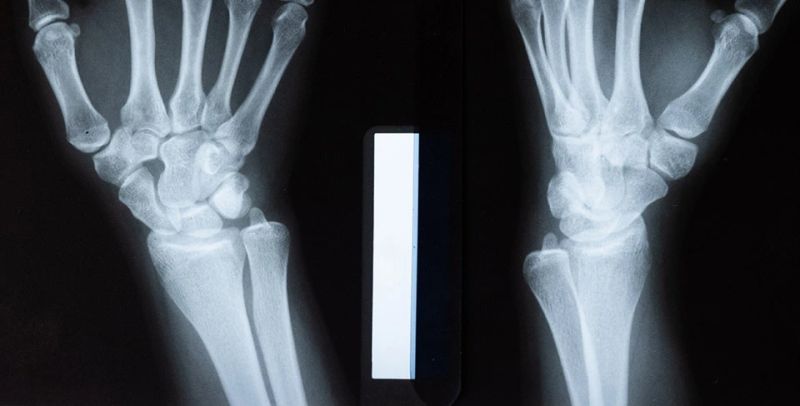

Rendgen ruke - snimanje nadlaktice i podlakticeRendgen ruke - snimanje nadlaktice i podlaktice

Rendgenski snimak ruke je dijagnostička metoda niskog rizika koja pomaže lekarima da identifikuju povrede, degenerativne bolesti ili nepravilan rast kostiju.

Snimanje može otkriti uzroke bolova, otoka i deformiteta, kao što su prelomi, ciste, tumori i infekcije.

Kako izgleda rendgenski pregled ruke?

Tehničar će tražiti da pristupite rendgen aparatu i objasniće vam kako da se pomerate ukoliko je potrebno načiniti snimke iz različitih uglova.

Sam rendgenski snimak nije bolan, međutim, rendgenski zraci se koriste za dijagnozu stanja kao što su prelomi kostiju, tumori i artritis. U nekim slučajevima, ova stanja mogu izazvati bol tokom procesa rendgenskog snimanja, jer se od pacijenta zahteva, radi što čistijih snimaka, da bude miran nekoliko minuta u položaju koji mu možda zbog preloma baš i ne prija.

Prednosti RTG snimanja nadlaktice ili podlaktice

Neke povrede, kao što je recimo slomljeni zglob, treba brzo dijagnostikovati i lečiti, I zato je rendgen veoma važan, jer ćete vrlo brzo dobiti potrebne rezultate snimanja. Mnogi moderni aparati za rendgensko snimanje prikazuju slike na ekranu računara čim se izvrši snimanje. Gusti predmeti, kao što su kosti ili nakit, biće prikazani belom bojom na snimku, dok će meka tkiva izgledati sivo.